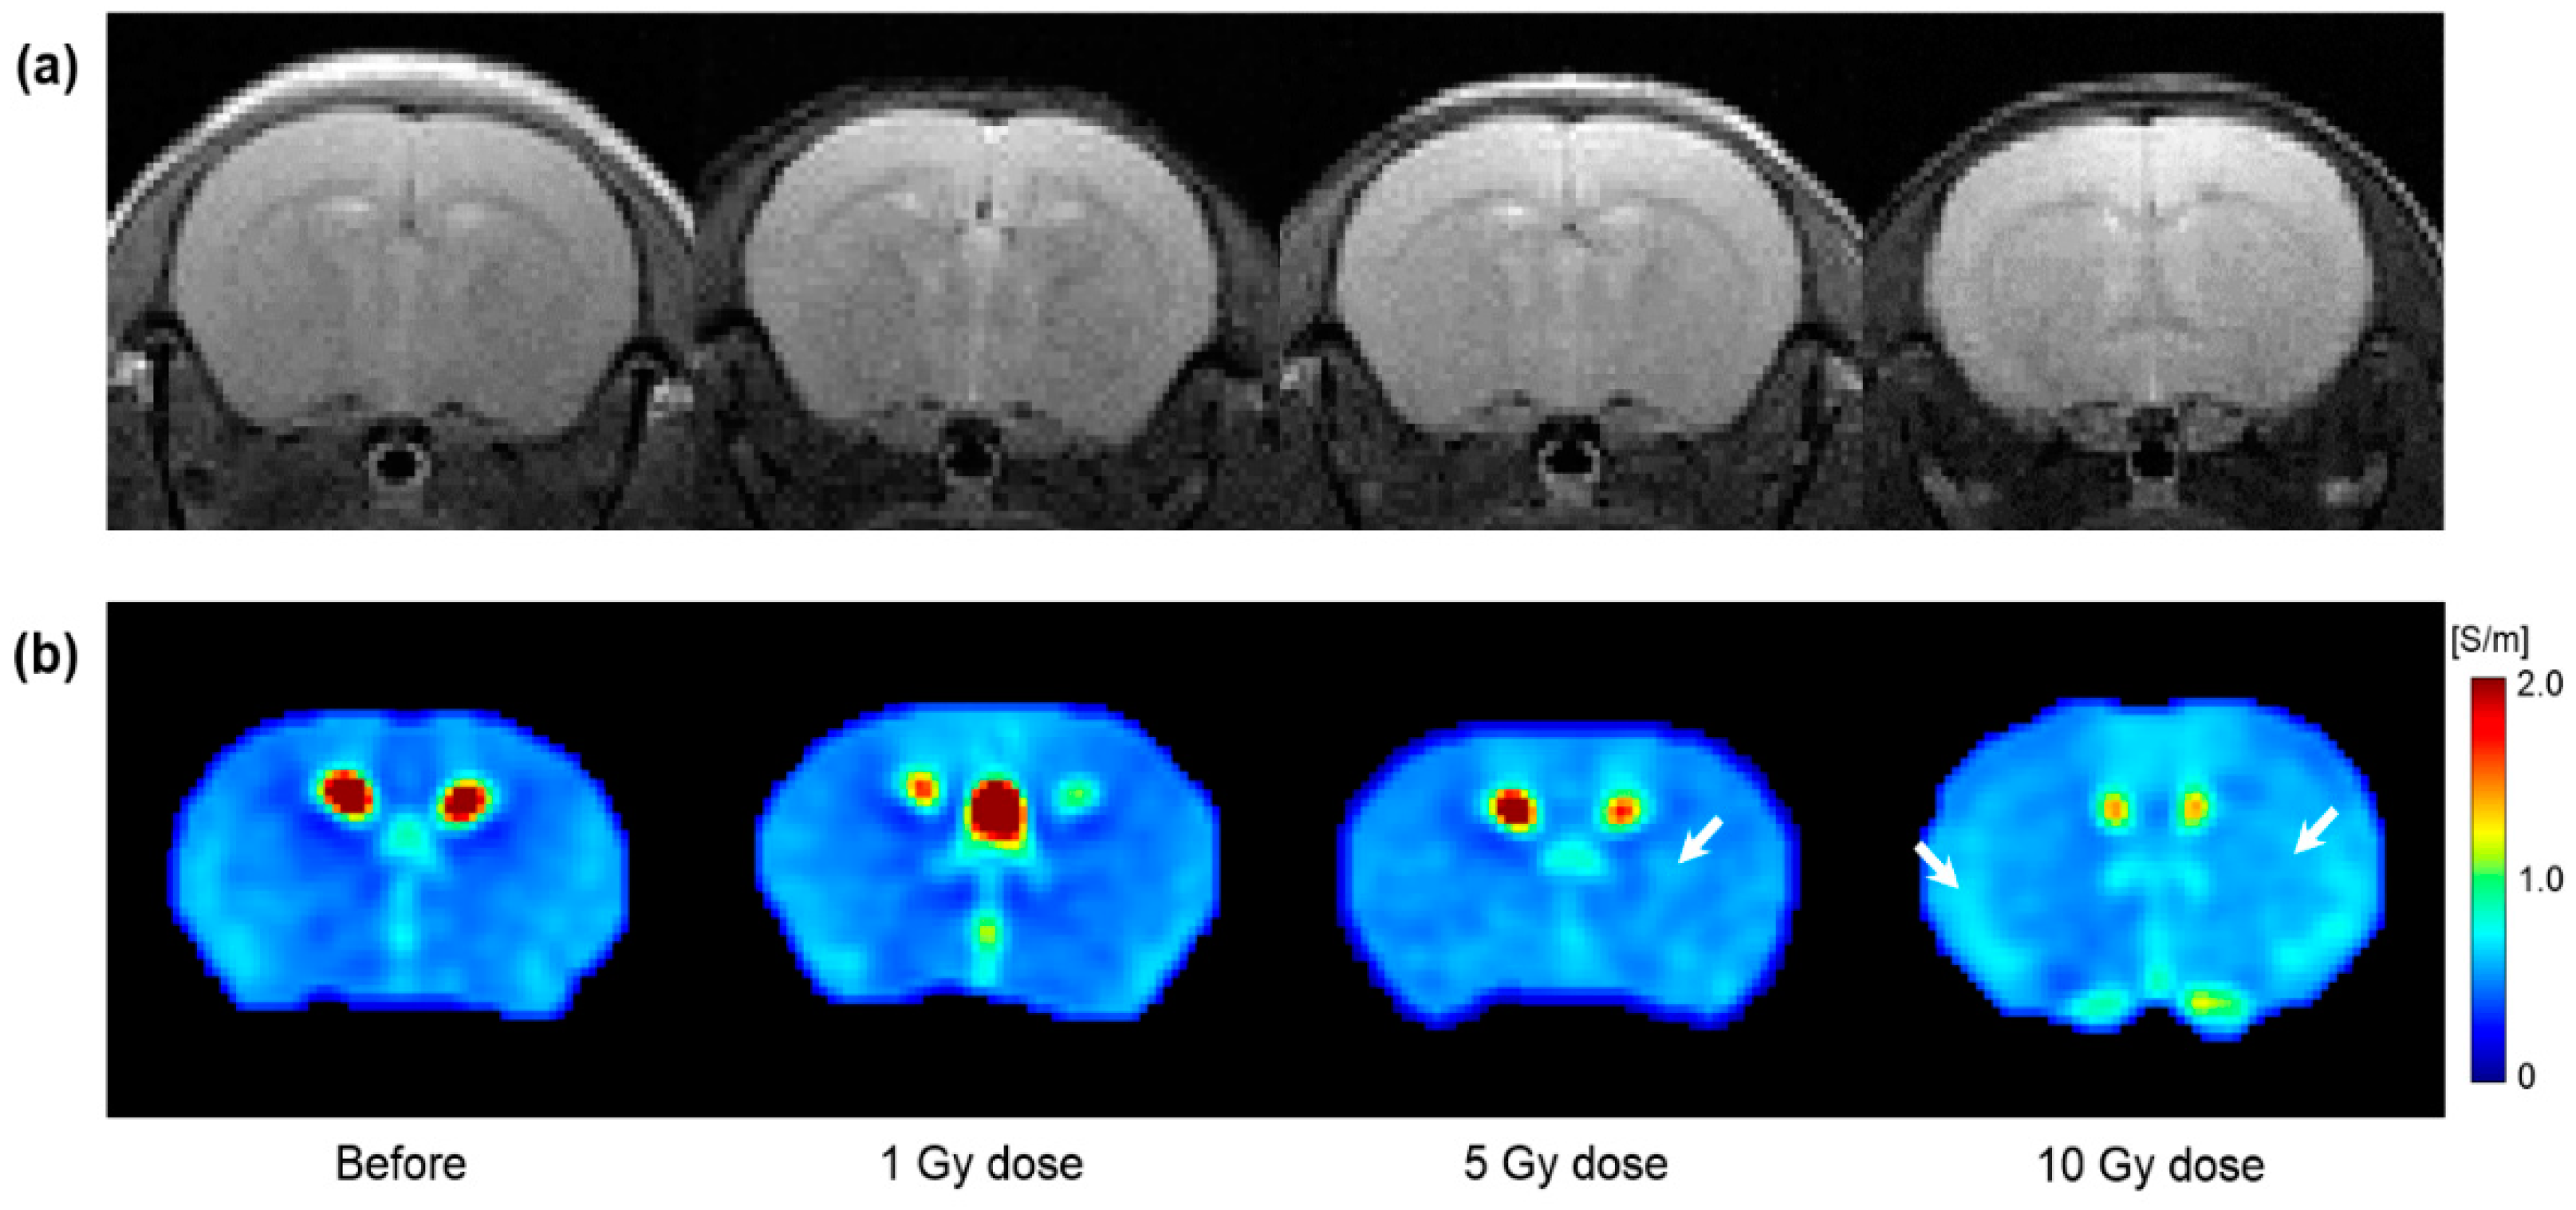

Figure 4 shows the T2WI and electrical conductivity image of in vivo mouse brains according to different irradiation doses. All images were acquired 1 day after irradiation. Compared to before irradiation, morphological differences were not observed in T2WI by the irradiation dose (Figure 4a). However, the conductivity images showed different contrasts by the irradiation dose (Figure 4b). Specifically, the conductivity image of the 10 Gy dose showed increased contrast throughout the brain region. The contrast was partially increased at 5 Gy. However, no clear contrast was observed in the 1 Gy dose.

Figure 4.

T2-weighted (a) and electrical conductivity (b) images of in vivo mouse brains with respect to tissue response by different irradiation doses. All images were acquired 1 day after irradiation. White arrows indicate the increase in conductivity contrast.

From the in vivo mouse brain imaging results, the morphological differences were not clearly observed at different doses and elapsed times after irradiation. This can be inferred from the previous report that the changes in T2 relaxation time were within 10% despite the neutron-beam irradiation [18]. On the contrary, electrical conductivity clearly showed contrast changes with different doses and elapsed times after irradiation. In comparison, at a single time point after irradiation (Figure 4), the conductivity contrast was clearly distinguished at the 10 Gy dose from the other two lower doses. This indicates the reliability of electrical conductivity in that 10 Gy is an appropriate dose calculated considering the weight of the mouse [6]. In addition, the conductivity contrast of 10 Gy showed a different pattern with the elapsed time (Figure 5). Unlike the other two doses, the conductivity of 10 Gy showed a more sustained tissue response and residual conductivity even 10 days after irradiation.